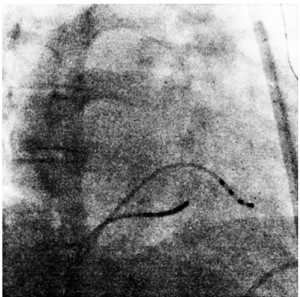

Transseptal puncture (TSP) is a critical step allowing access from right atrium to left atrium in cardiac interventions. The operation relies heavily on real-time X-ray imaging and often involves subjective decision-making needing experience. Recent advancements in artificial intelligence (AI), particularly visual foundation model offer promising solutions to enhance the precision and consistency of TSP.

This study aims to develop and validate an AI method that automatically identifies the ideal TSP site using only the CS catheter as a reference in X-RAY image. This approach seeks to replicate the decision-making process of experienced clinicians, thereby improving the accuracy and safety of the procedure.

A pilot study enrolled 101 patients in one center. Three experienced senior practitioners are responsible for labeling these images. To learn information from limited X-RAY images, we design a co-training framework based on Segment Anything Model (SAM) to fine-tune the decision module for TSP by combining visual prompts of the three bounding boxes (heart edge, spine, and coronary sinus electrode). The input images are captured before puncture and resized to 512*512. The candidate puncture area is set as a circle centered at actual puncture point with a radius of 10 pixels.

Images from 80 patients were used to fine-tune the decision module, while 21 for validation. The Intersection over Union (IoU) on validation set is 70.22% for the pre-defined candidate TSP circle. In validation, the success rates of the predicted TSP point (the center of the predicted area) falling within radii of 5, 10, 15 pixels cantered on the actual TSP site are 56.30%, 72.01% and 83.54%, respectively.